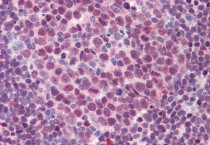

ARG64671 anti-PU.1 antibody IHC-P image

Immunohistochemistry: Paraffin-embedded Human colon tissue. Antigen Retrieval: Steam tissue section in Citrate buffer (pH 6.0). The tissue section was stained with ARG64671 anti-PU.1 antibody at 3.75 µg/ml dilution followed by AP-staining.